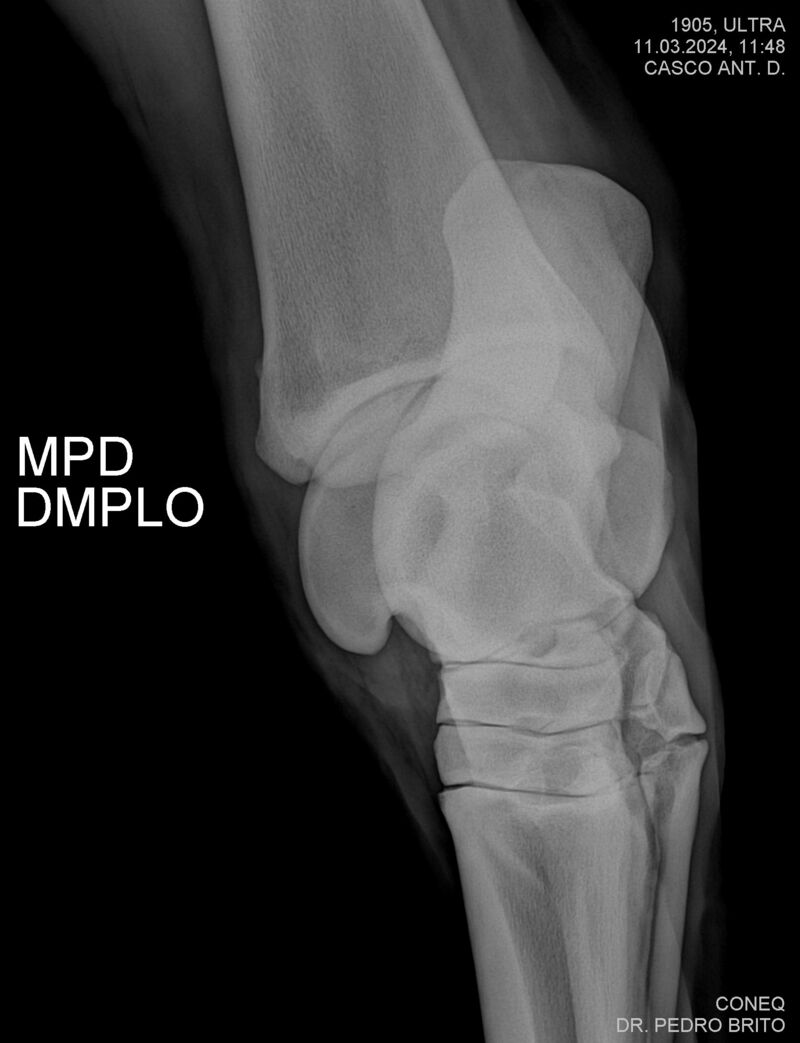

ULTRA DO CACH

Raça: BRASILEIRO DE HIPISMO

Sexo: CASTRADO - CASTRADO

Nascimento: 22/11/2020

Altura Aproximada: 1,67

Pel.: CASTANHO

Registro: 25966-BH

Vend.: HARAS CACHOEIRINHA

Local : PIRASSUNUNGA/SP